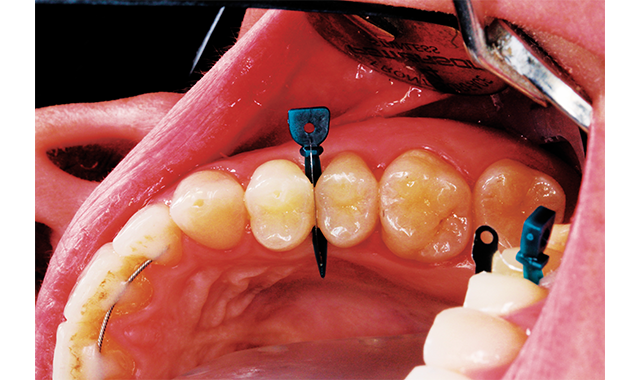

How to achieve beauty, form, and function using the stamp technique

Follow these steps to create a great restoration and gain the “stamp of approval.”

by Peter A. Gardell, DDS

Featured product: Tetric EvoFlow Bulk Fill from Ivoclar Vivadent

If it’s working why change it? If we have an occlusal surface that has been functioning, why do we feel the need to take a chance by rebuilding it by hand? There is no reason to have to re-invent the wheel with these situations.